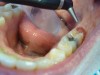

3. After the initial pass with the laser, the inflamed gingiva bled slightly and the surgeon defocused the beam by increasing the nozzle-to-tissue distance to quickly obtain hemostasis (Figure 6). Note the excellent visualization and the clear operatory field.

Fig 6. Excellent hemostasis after the completed ablation of the inflamed gingiva.

Figure 6